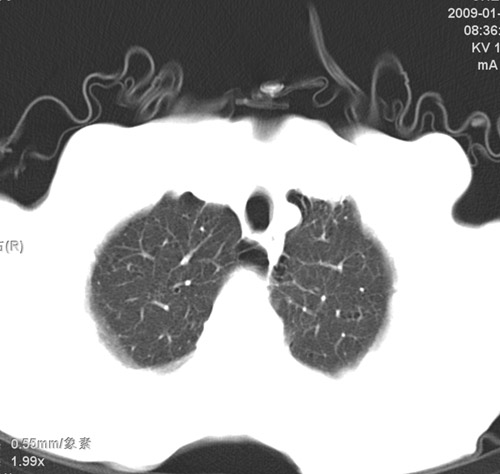

标题: CT17529:男 76 胸背部不适半月 胸透支气管炎 行CT检查 [打印本页]

标题: CT17529:男 76 胸背部不适半月 胸透支气管炎 行CT检查

意见 老年肺 少许炎症 肺大泡 右肺门略大 但支气管通畅  请各位高手指教如何下意见

间质纤维化伴少许炎症!另:肺大泡形成!

慢支肺气肿,肺动脉高压.